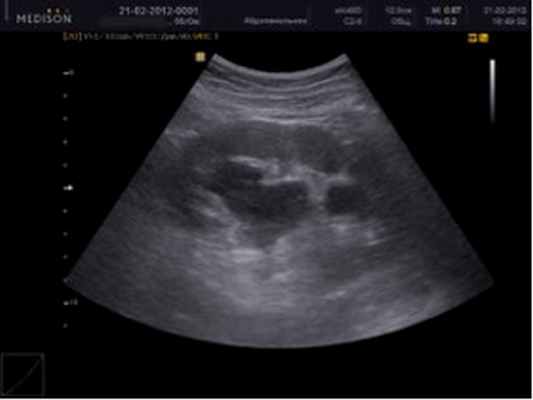

Выявление гидронефроза - непростая задача, требующая внимательного изучения состояния и жалоб пациента, его анализов. Нередко для диагностики гидронефроза используется УЗИ и рентгенография мочевых путей.

При первых же болях во время мочеиспускания лучше всего обратиться в больницу к профессиональному врачу, чтобы болезнь не оказалась запущенной. Если в целом рассматривать диагностику гидронефроза, то зачастую это УЗИ, с помощью которого проверяется работа мочевого пузыря и функционирование почек человека. Вылечить гидронефроз реально, но и для этого есть свой специальный метод – нефростомия, о котором более подробно будет рассказано позже.

Если больной жалуется на то, что периодически он ощущает колики в области живота, то диагностика позволяет сделать катетеризацию мочевого пузыря. В большинстве случаев многие клиники прибегают к проверенному методу диагностики – УЗИ. Это комплексный подход врача к тому, чтобы понять, с чем он имеет дело, иногда используются и рентгеноконтрастные исследования. При помощи рентгена можно легко определить, как работает выделительная функция при активной почке.

o Ультразвуковое исследование почек — позволяет определить увеличение и размеры лоханки и чашечек почки, степень их расширения, толщину ткани почки.